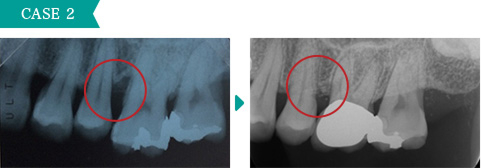

歯茎が腫れて痛みもあり、歯周病が中程度に進行していました。簡単な歯周外科処置をすることによって歯ぐきの腫れが改善して健康な状態に戻りました。